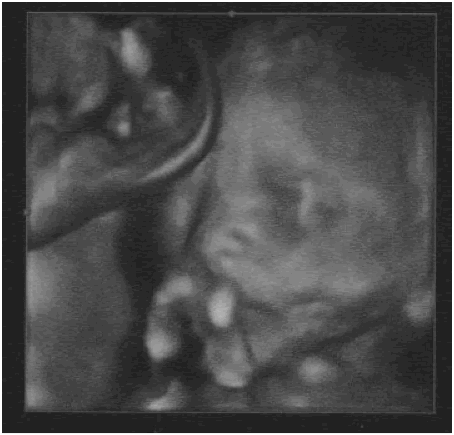

Cerise sur le gâteau, nous avons eu de superbes clichés des visages de Zoé et Timothée !

| Zoe a 24 semaines | Timothee a 24 semaines |